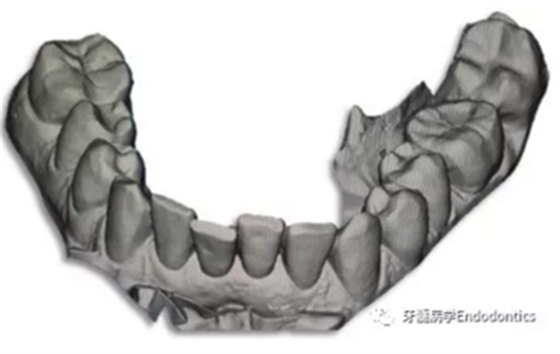

31、41叩痛明顯,牙冠變色(圖1)。溫度和牙髓電活力測(cè)試無(wú)反應(yīng)。兩張從不同角度拍攝的x線(xiàn)片顯示,相對(duì)于側(cè)切牙,雙側(cè)下中切牙都有嚴(yán)重的根管鈣化(圖2)。41有明顯根尖周暗影,31根尖周暗影不明顯。為進(jìn)一步證實(shí)31是否存在根尖周病變,同時(shí)精細(xì)觀(guān)察31、41的復(fù)雜結(jié)構(gòu),根據(jù)歐洲牙髓病學(xué)會(huì)CBCT應(yīng)用指南(2014),對(duì)患牙拍攝小視野、高分辨率CBCT。CBCT影像證實(shí)31、41均伴有根尖周炎和嚴(yán)重的根管鈣化(圖3)。距離根尖4mm可見(jiàn)根管影像。 由于患牙根管解剖結(jié)構(gòu)較為復(fù)雜,筆者決定使用特殊設(shè)計(jì)的微型鉆頭(直徑0.85mm)進(jìn)行“數(shù)字化導(dǎo)航牙髓治療”。 因此對(duì)下頜進(jìn)行口內(nèi)掃描(圖4)。用coDiagnostixTM軟件(Dental Wings Inc.,Montreal,Canada)將CBCT和口內(nèi)掃描的數(shù)據(jù)進(jìn)行處理,該軟件主要用于引導(dǎo)種植。通過(guò)該軟件對(duì)兩個(gè)掃描圖像進(jìn)行疊加后,虛擬鉆頭尖端沿牙長(zhǎng)軸對(duì)準(zhǔn)根管下段可見(jiàn)部分(圖5)。三維檢查虛擬鉆的正確位置。

圖4.下頜牙口內(nèi)表面掃描的表面鑲嵌語(yǔ)言(stl-)數(shù)據(jù)。